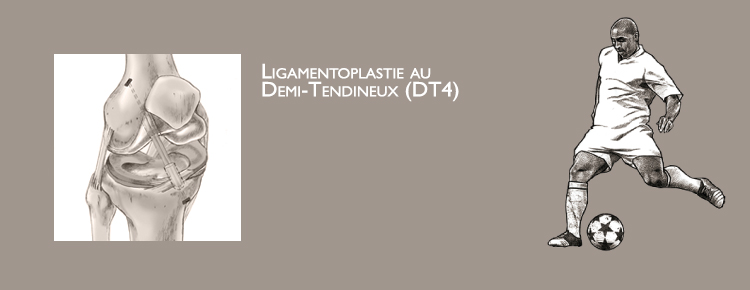

Le but de la ligamentoplastie du croisé antérieur est de stabiliser le genou permettant la reprise de toutes les activités sportives, et d’éviter les lésions cartilagineuses ou méniscales limitant ainsi la dégradation de l’articulation.